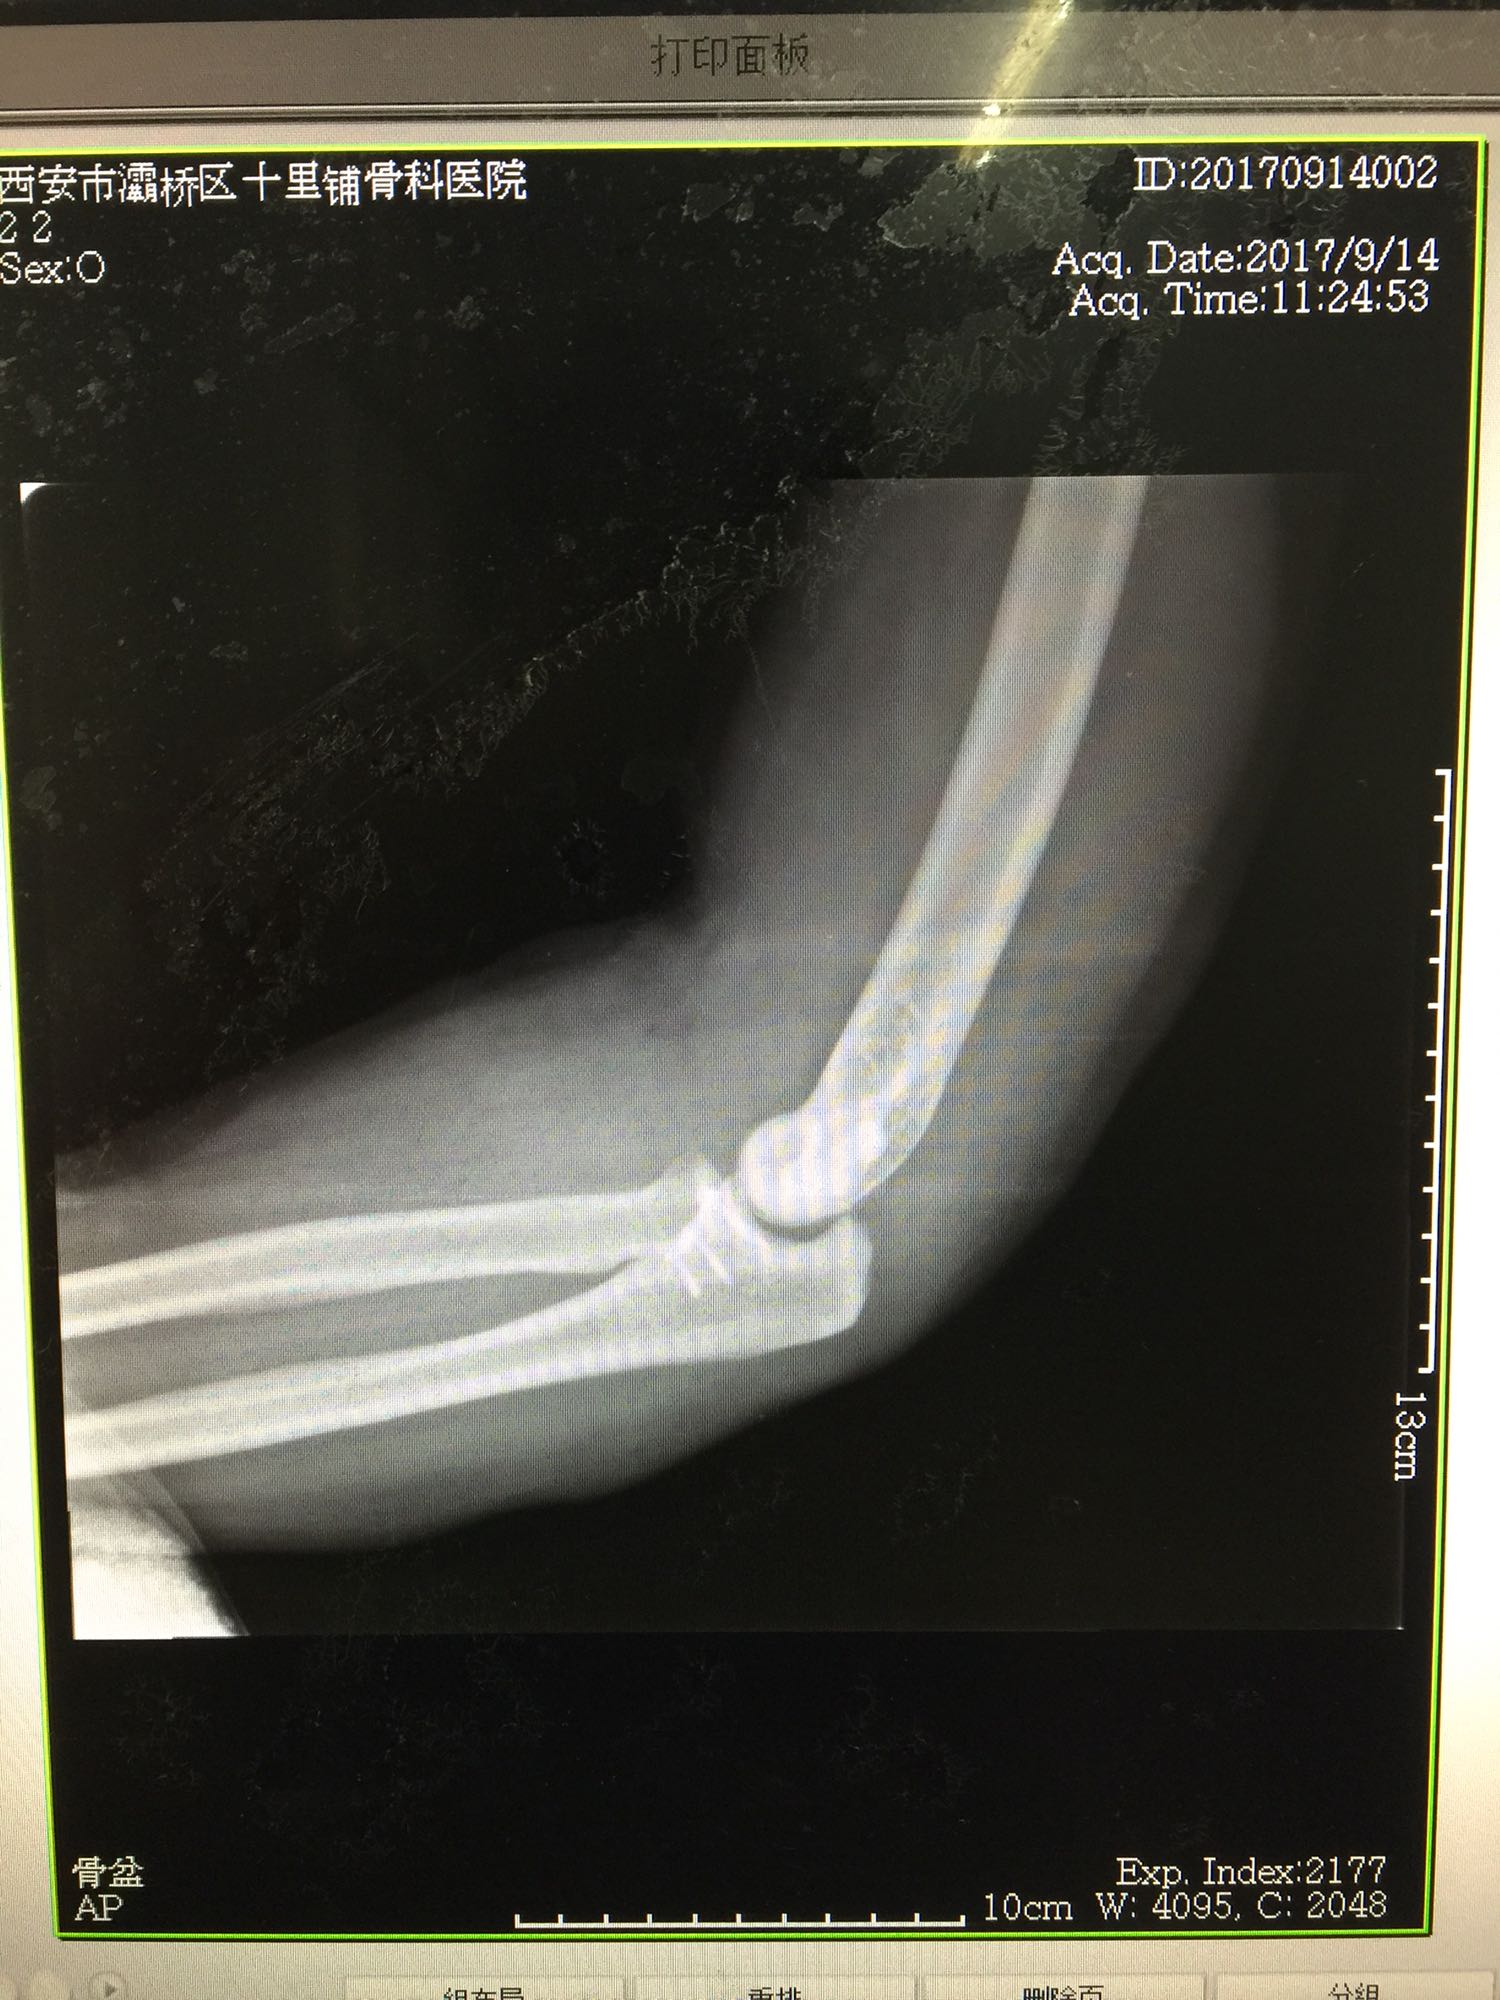

1、左尺骨冠状突骨折;2、左肱骨外髁撕脱骨折 治疗:入院后伤肢石膏外固定,给予局部冷敷消肿治疗,于伤后一周行骨折手术治疗,先行前内侧切口复位固定冠状突骨折,活动肘关节发现关节明显不稳定,随取外侧切口,复位固定肱骨外髁,修补外侧副韧带,肘关节明显稳定。术中术后片子如下

患者目前功能恢复满意,骨折愈合。